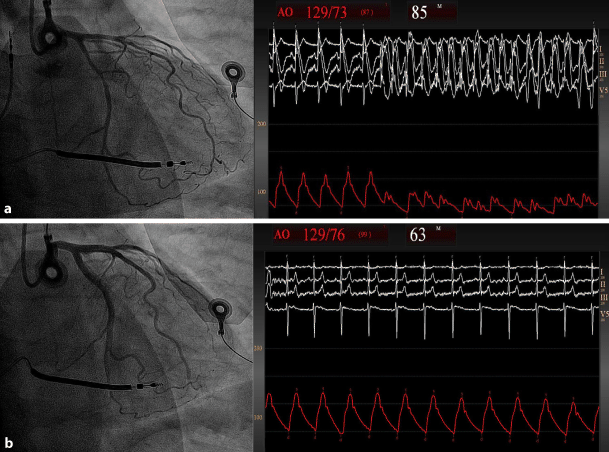

Polymorphic ventricular tachycardia can be a detrimental consequence of coronary vasospasm [1]. The pathophysiology of vasospastic angina (VA) is poorly understood, although the disease has been linked to sympathetic hyperactivity [24]. We present a 52-year-old male smoker with ventricular fibrillation (VF) 2 years ago. Work-up revealed no signs of structural heart disease or obstructive coronary disease. We implanted an implantable cardioverter defibrillator (ICD). Several episodes of non-sustained polymorphic ventricular tachycardia and ICD shocks due to VF ensued, despite maintenance therapy with isosorbide 100 mg, metoprolol 50 mg, verapamil 300 mg, amiodarone 200 mg. Methylergometrine testing confirmed VA as the cause of VF (Fig. 1a,b). To reduce sympathetic hyperactivity, bilateral renal denervation was performed using the ReCor Paradise system. The patient remained free from episodes of angina and ventricular arrhythmias at 6 and 12 months. Ambulatory blood pressure and mean heart rate remained stable between baseline and 6 months (108/60 mm Hg vs. 113/71 mm Hg and 60 bpm vs. 60 bpm, respectively). Renal denervation could be a safe and effective treatment for normotensive patients with severe VA despite optimal medical therapy.

Fig. 1

Methylergometrine testing revealed severe coronary spasms in multiple coronary segments resulting in ventricular tachycardia and haemodynamic collapse (a). This quickly resolved after intracoronary nitrates (b)